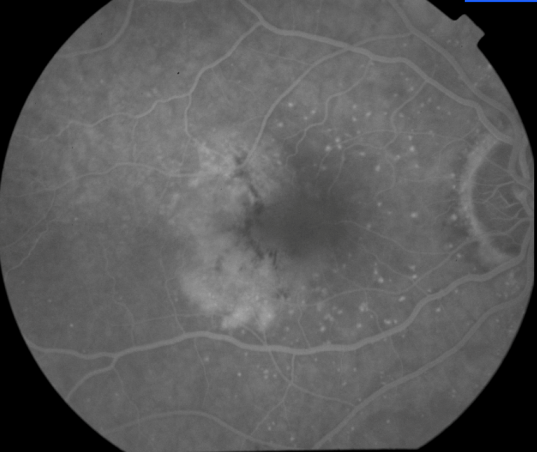

OD Red-Free: Pre-Injection: Arterial: A-V: Venous: Recirculation: Late:

OS Red-Free: Venous: Recirc: Late:

Impression